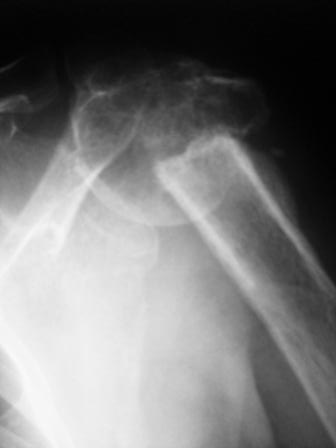

Уважаемые коллеги! Госпитализирована больная 51года. Травма - перелом

хирургической шейки плеча в феврале 2009г. Лечилась по месту

жительства Лонгетной гипсовой повязкой. На фоне сформировавшегося

ложного сустава работает маляром. Объем движений и сила естественно

ограничены. При обсуждении тактики лечения возникли разногласия по поводу вида остеосинтеза и его

целесообразности.